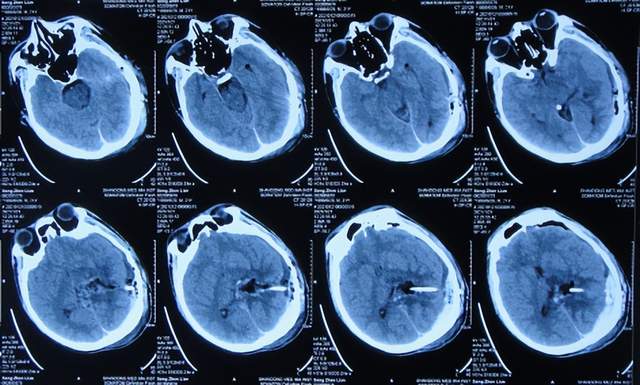

入院后5天即2021年1月18日,查头颅CT增强示颅内占位(图-4)。

图-4:2021年1月18日头颅CT增强

入院后7天即2021年1月20日,进行了颅内占位切除术,留置引流管(图-5)。

图-5:2021年1月20日头颅CT

颅内占位切除术后次日即2021年1月21日,查头颅CT示脑瘤术后改变(图-6)。

图-6:2021年1月21日头颅CT

颅内占位切除术后第2天即2021年1月22日,头痛基本消失,脑瘤病理回报脑膜瘤;查头颅CT示脑室周水肿(图-7)。

图-7:2021年1月22日头颅CT

脑膜瘤术后第5天即2021年1月25日,查头颅是示水肿减轻(图-8)。

图-8:2021年1月25日头颅CT

术后第7天即2021年1月27日,拔除脑室外引流管(图-9),改行腰大池引流并给予抗感染治疗。

图-9:2021年1月27日头颅CT